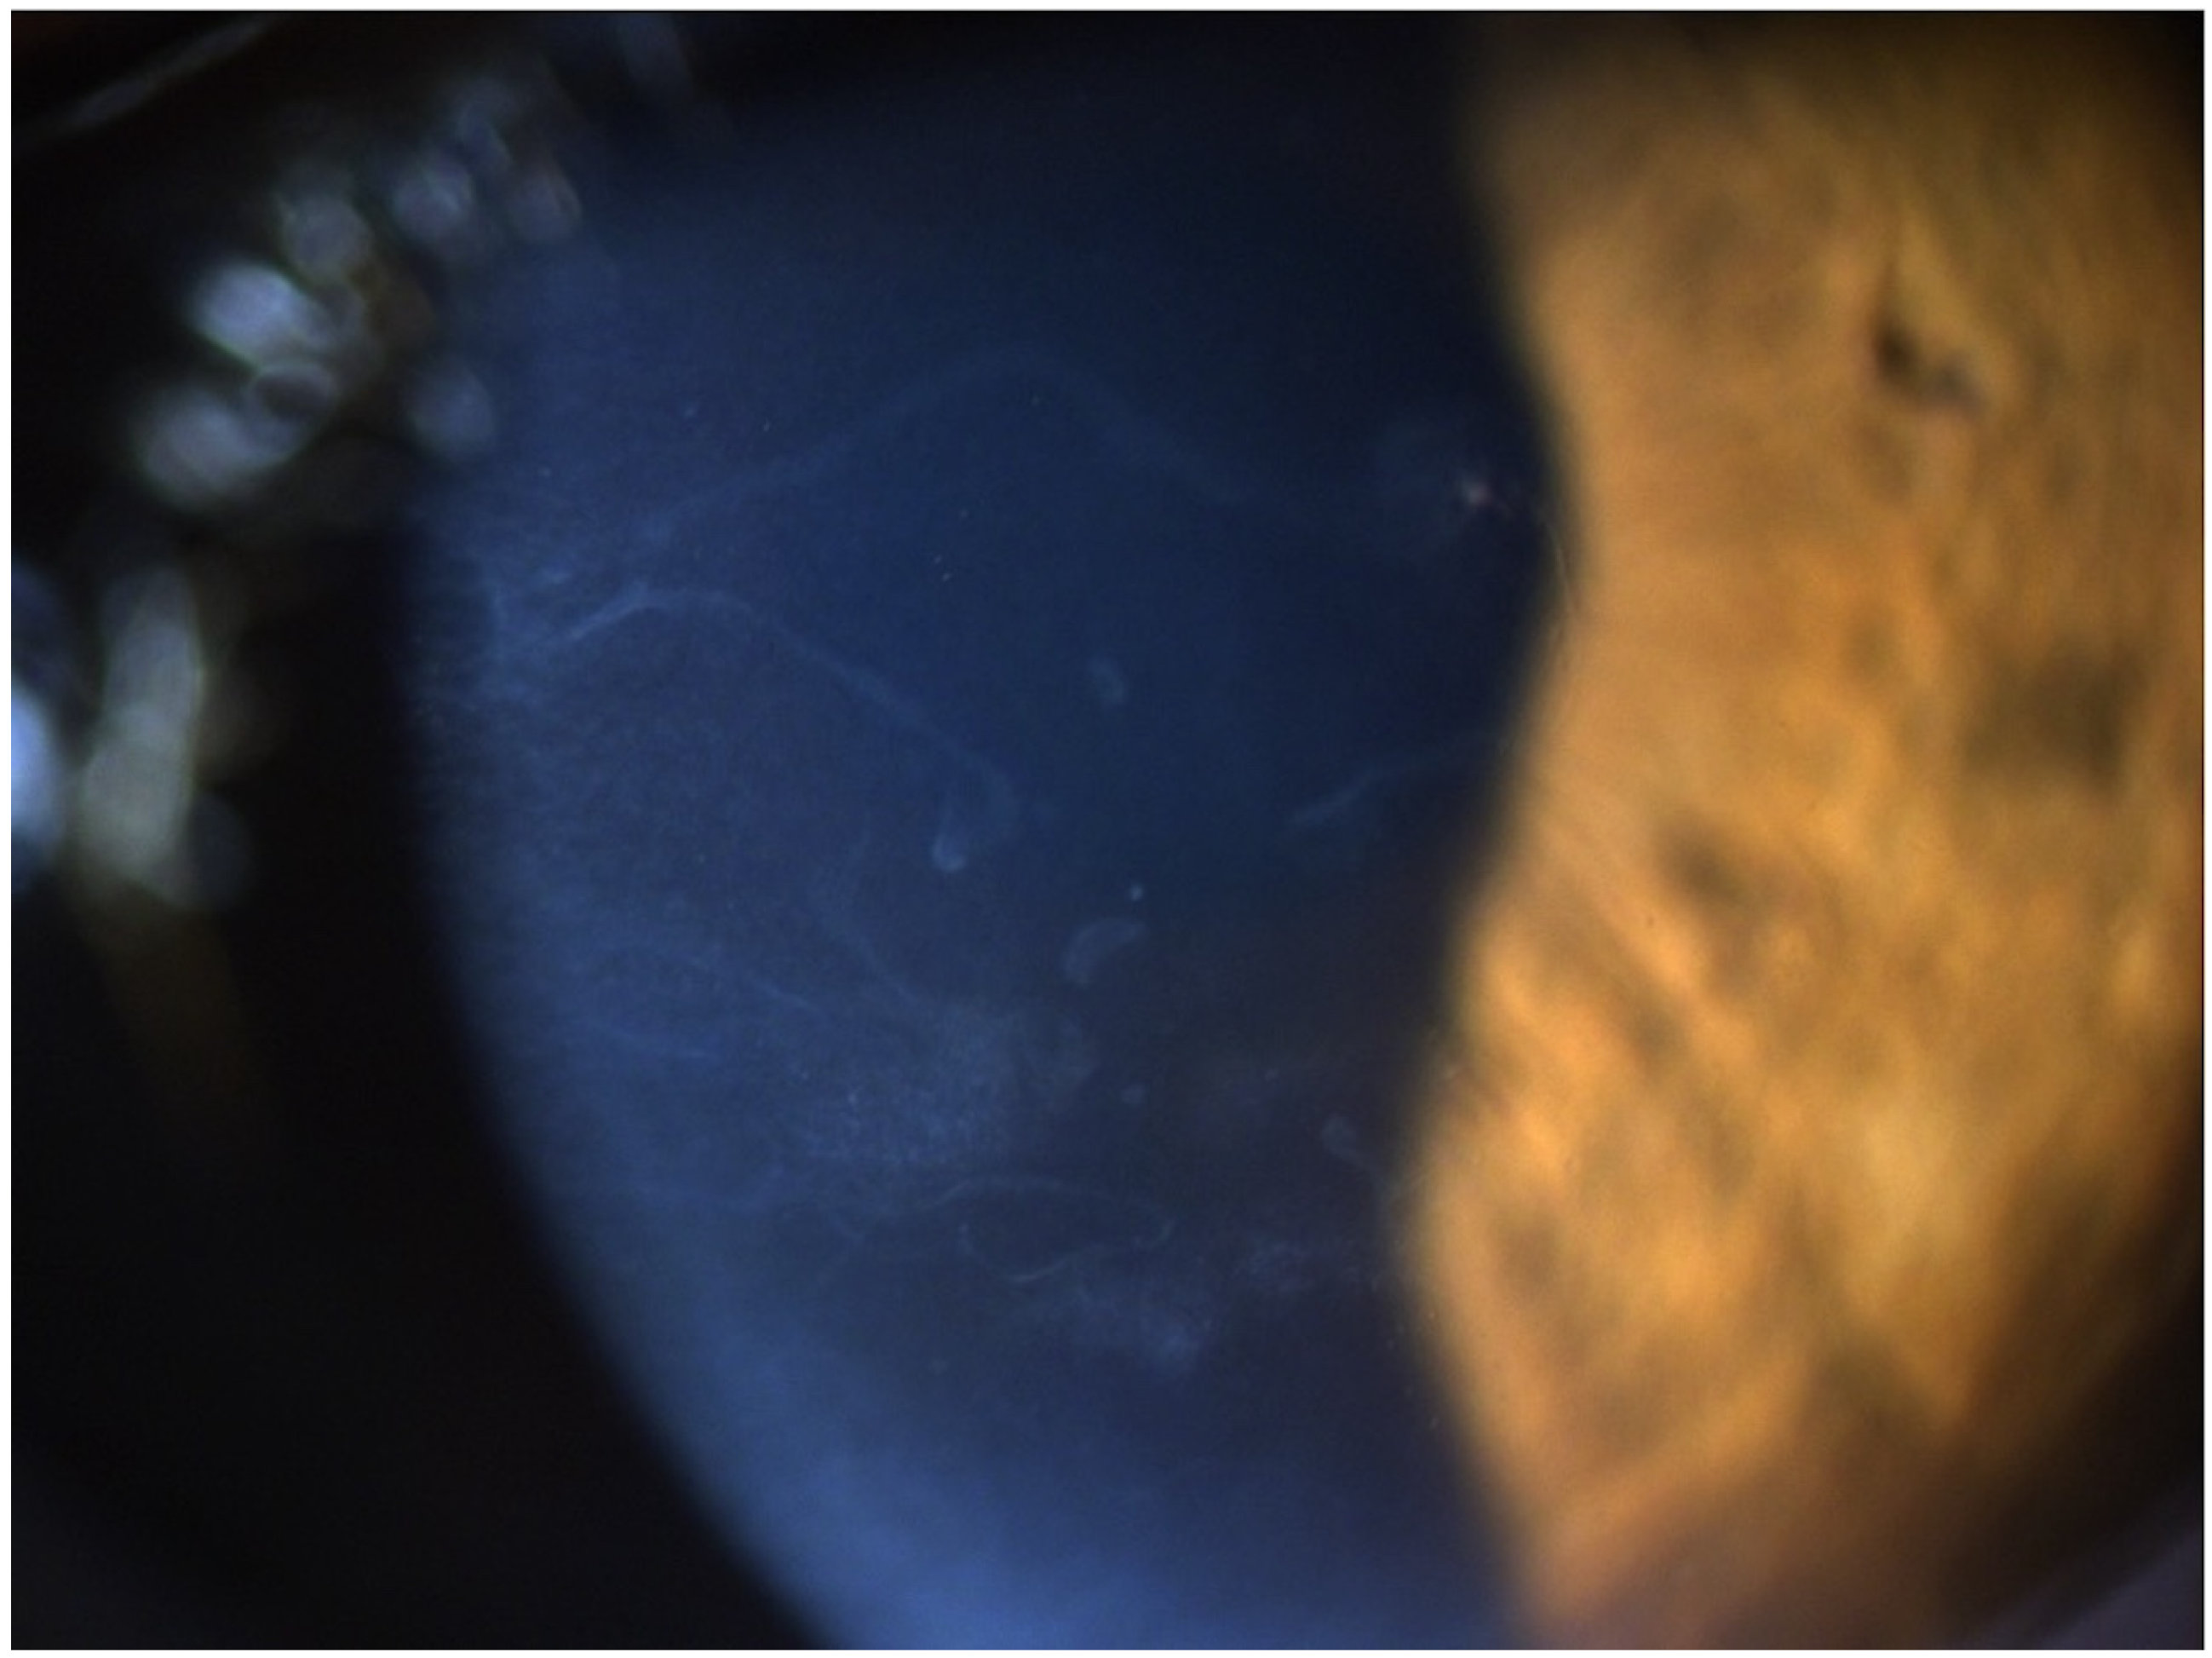

Combined Rotating Ultra-High-Resolution Spectral Domain OCT and Scheimpflug Imaging for In Vivo Corneal Optical Biopsy

1.3. The Pentacam® Cornea OCT

2. Materials and Methods

3. Results